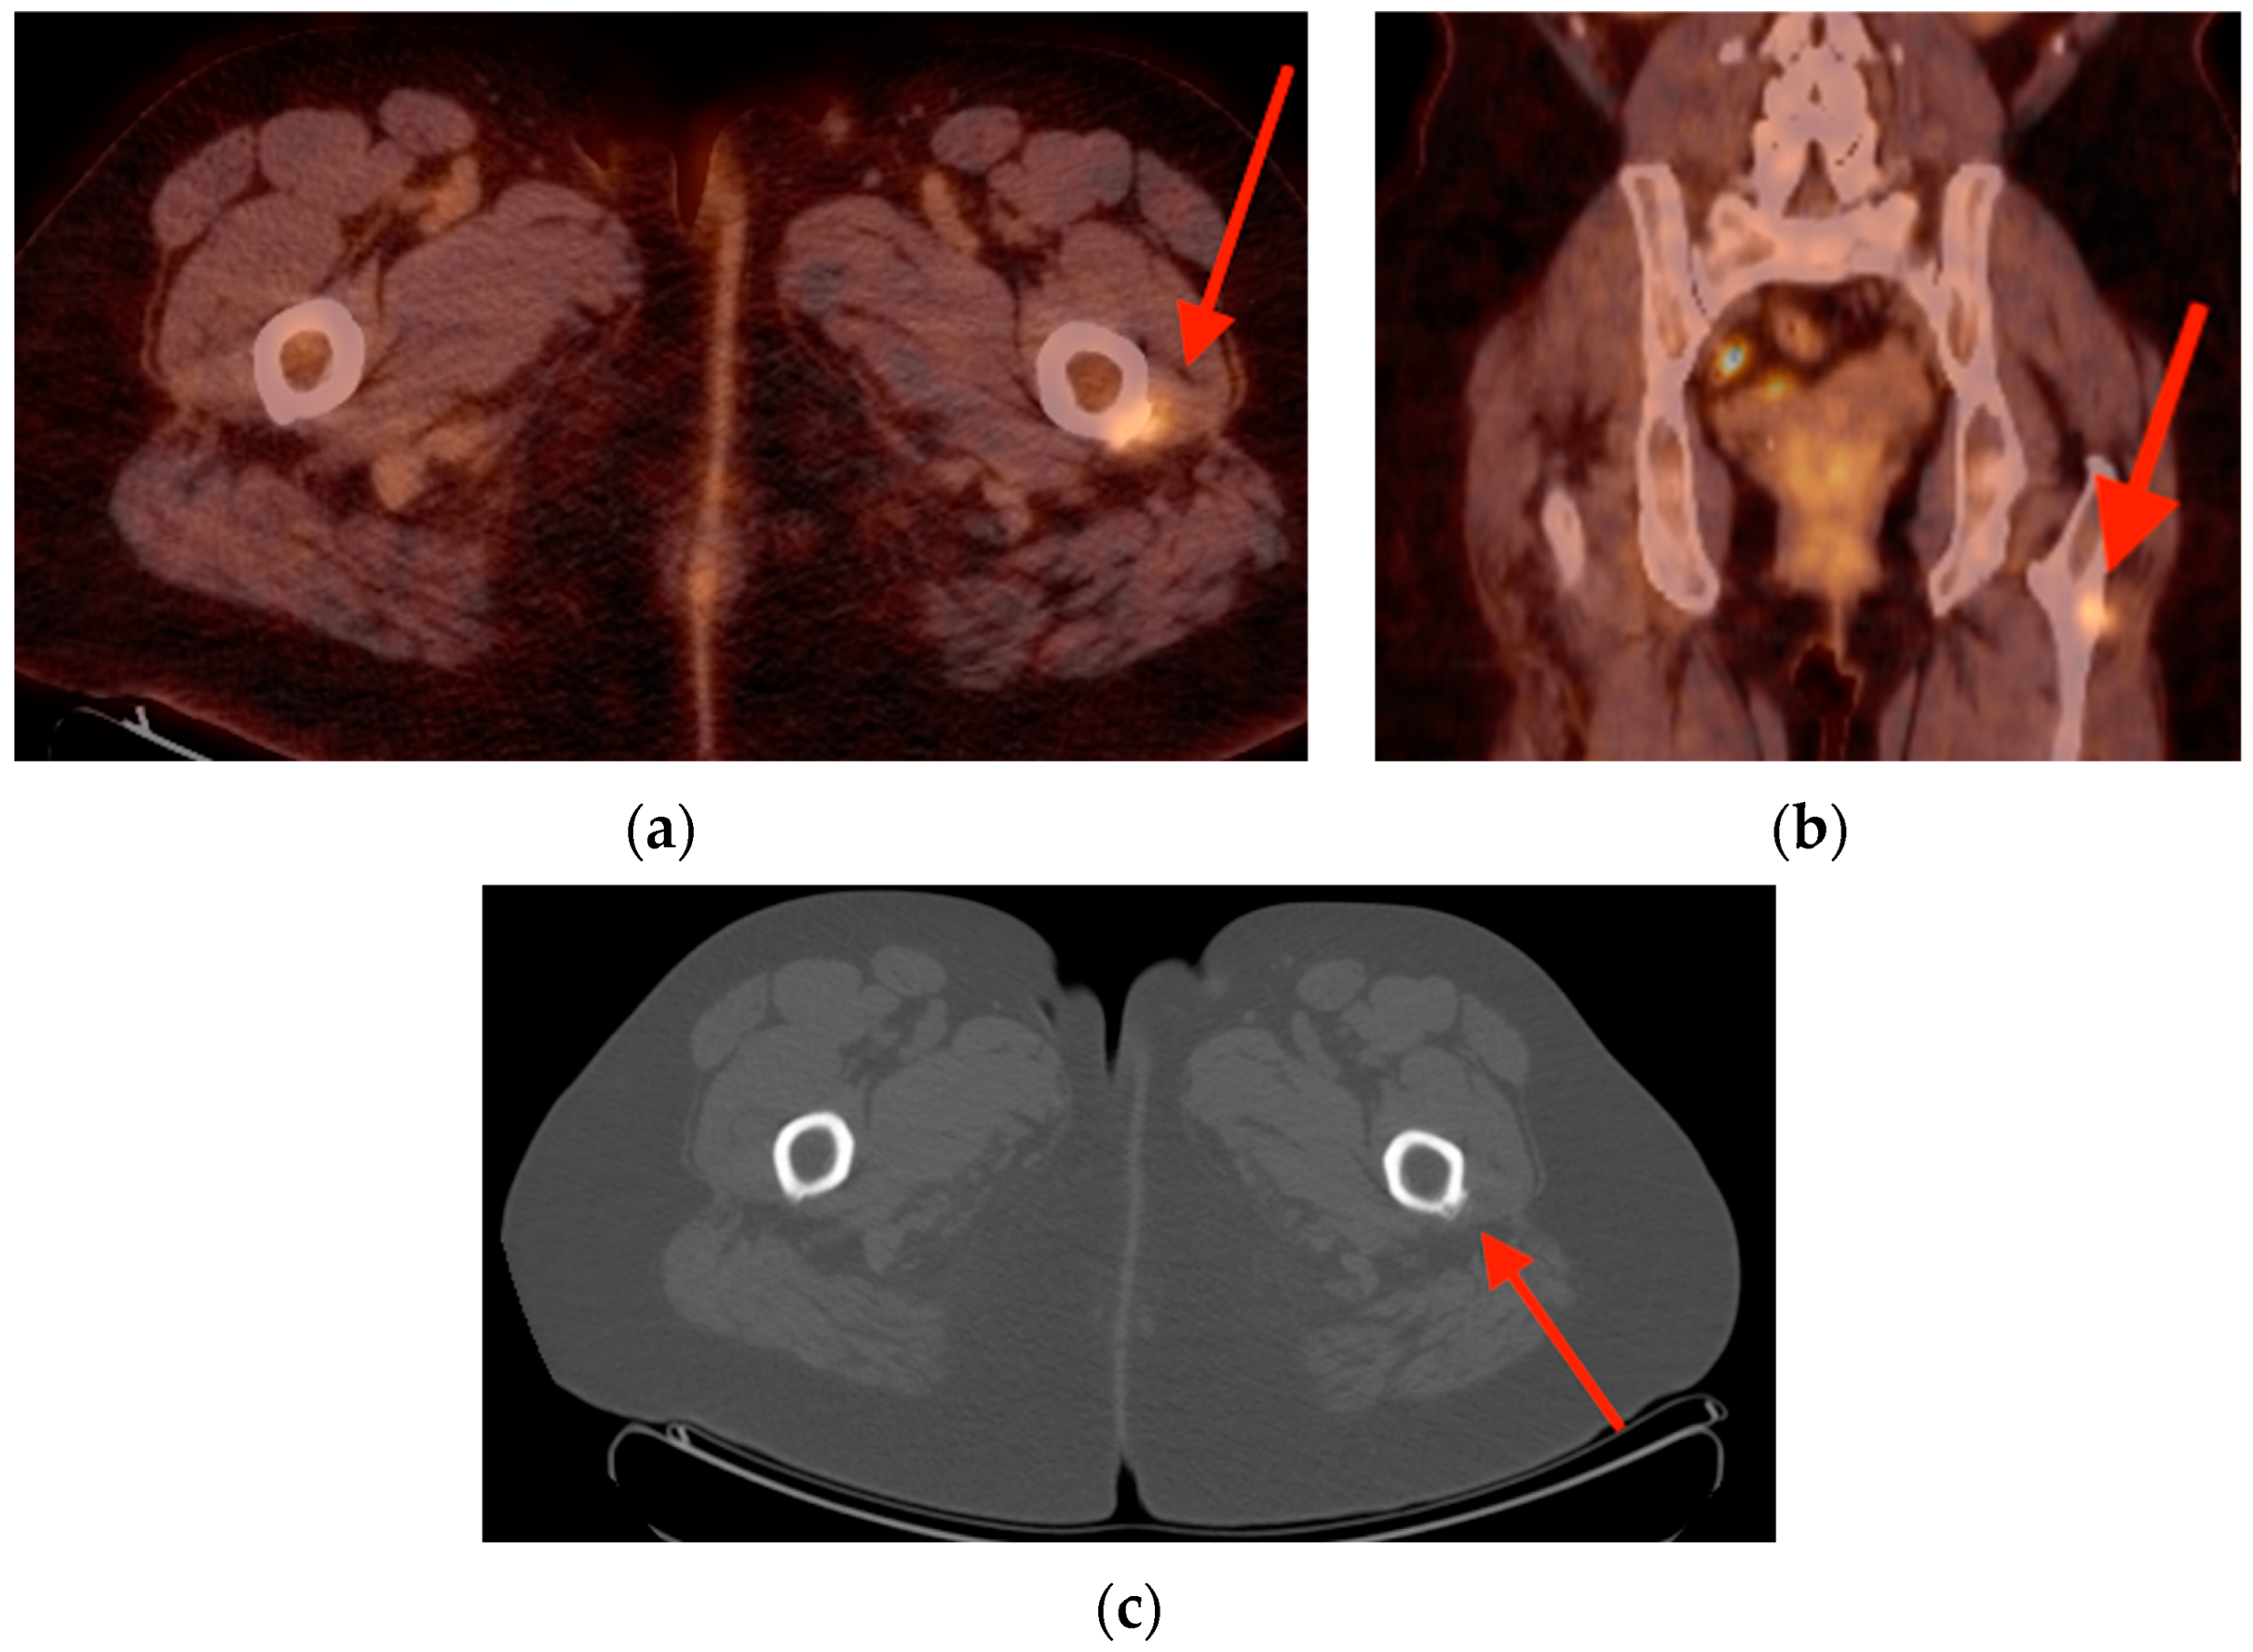

2.1. Fracture

- Chung, Y.K.; Lee, Y.K.; Yoon, B.H.; Suh, D.H.; Koo, K.H. Pelvic Insufficiency Fractures in Cervical Cancer After Radiation Therapy: A Meta-Analysis and Review. In Vivo 2021, 35, 1109–1115. [Google Scholar] [CrossRef]

- Salavati, A.; Shah, V.; Wang, Z.J.; Yeh, B.M.; Costouros, N.G.; Coakley, F.V. F-18 FDG PET/CT findings in postradiation pelvic insufficiency fracture. Clin. Imaging 2011, 35, 139–142. [Google Scholar] [CrossRef]